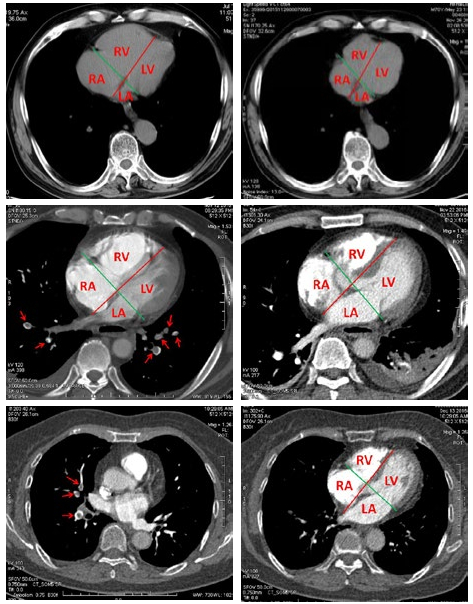

利用四心腔分界线m线与n线作为测量基线,可以对患者不同时间胸部CT或CTPA图像各心腔LR径、AP径进行有效测量对比。POI≥50%时,常常可以发现右心明显增大,并且可以在CTPA检查确诊前就及时发现PE患者出现有急性右心增大(图 1A、B),同时可以观测评价治疗后右心形态恢复情况(图 1C、D)。POI < 50%时,右心增大不明显(图 1E、F)。

| A、B:PE患者(POI≥50%),男,71岁,以头晕1小时急诊就诊,行胸部CT(图 1A)与8个月前胸部CT(图 1B)对比,以四心腔分界线m线(红色线)与n线(绿色线)作为测量基线,右心房(RA)与右心室(RV)明显增大,左心房(LA)与左心室(LV)可见缩小,各心腔变化,以左右径(LR)为明显;C、D:PE患者(POI≥50%),男,63岁,CTPA(图 1C)两肺动脉多发充盈缺损(↗),室间隔可见运动伪影明显,以m与n线作为测量基线,右心房(RA)与右心室(RV)明显增大。10天后复查(图 1D),肺动脉内大部分栓子消失,右心增大缓解。E、F:PE患者(POI<50%),女,74岁,CTPA(图 3a)两肺动脉多发充盈缺损(↗),四腔心层面(图 3b),以m与n线作为测量基线,右心房(RA)与右心室(RV)无明显增大,各心腔比例未见明显异常 图 1 PE患者胸部CT或CTPA图像 Fig 1 Images of CT and CTPa of PE patients |